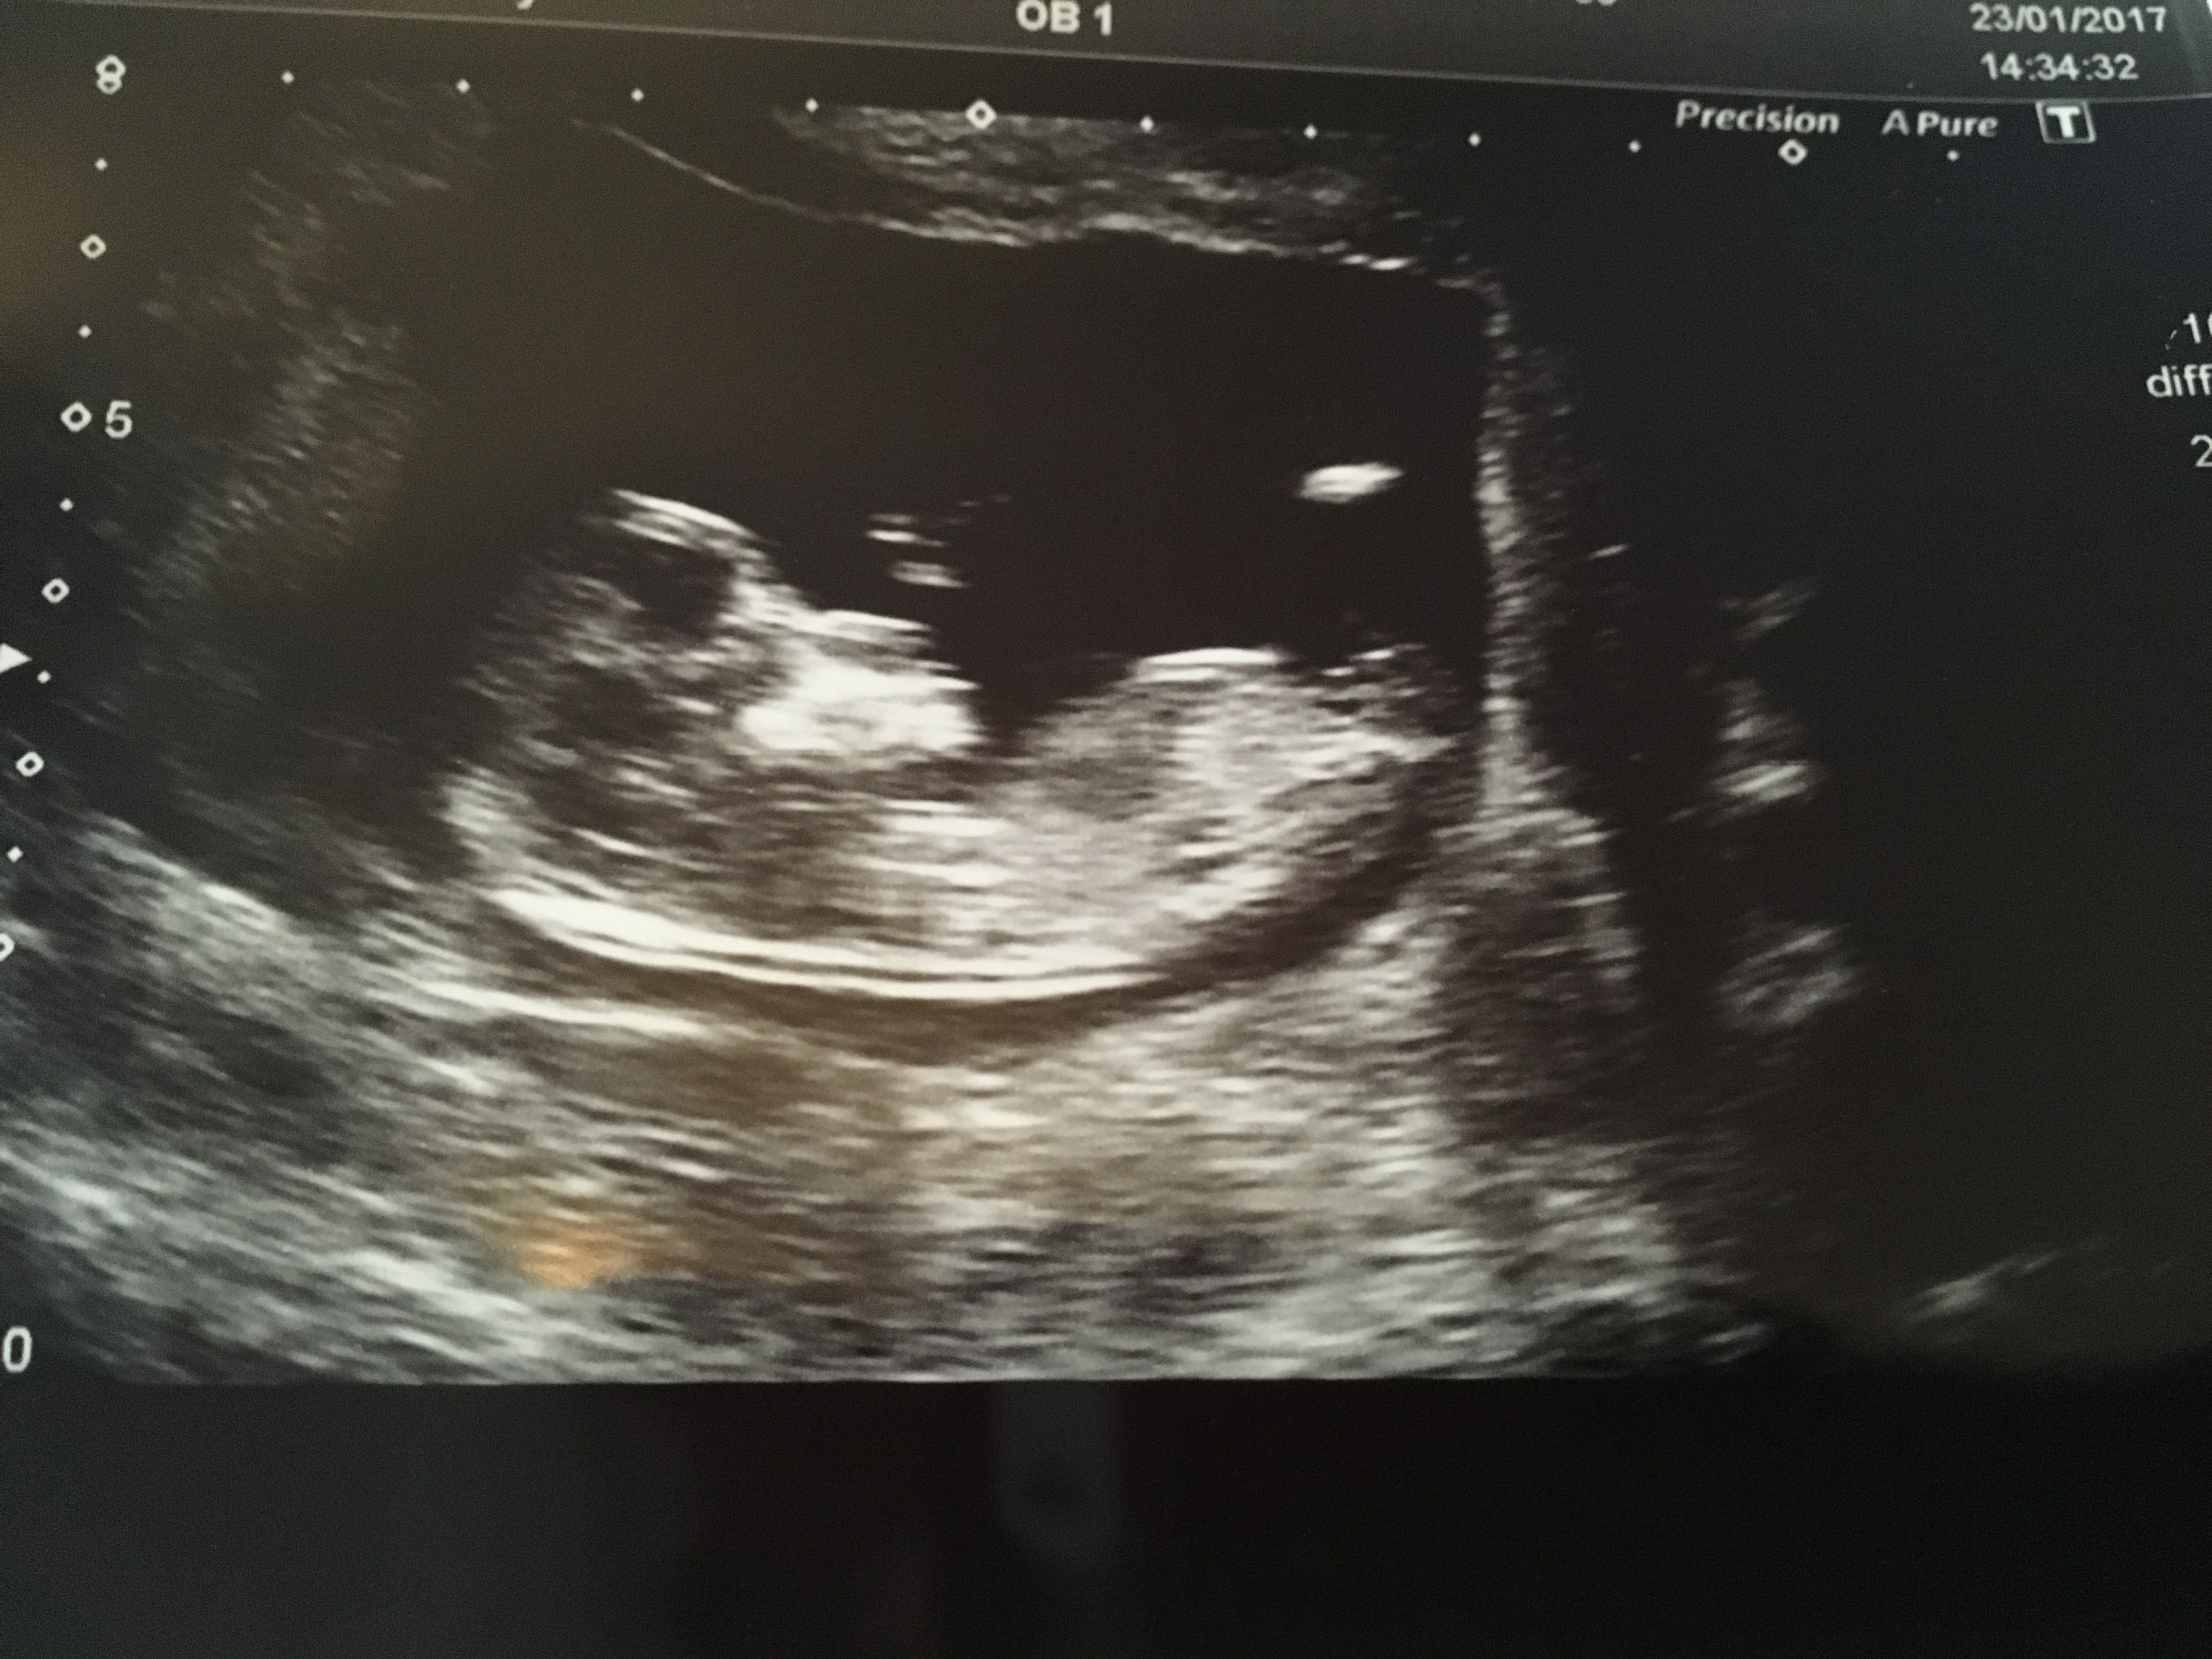

I don't know if the picture has attached properly but this is my 12 week scan and I just wanted to know if any one could tell if baby is a boy or girl? I know it's not the best of pictures!! I only have 6 days until I find out at my 20 week scan!!! Thank you x x x x